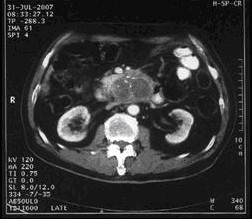

男,68岁,2006年12月14日,CT扫描发现胰头占位性病变,6.0×4.7cm2,腹膜后淋巴结转移,伴肝内多发转移灶。艾恒+希罗达化疗3疗程无效(图1)。2007年4月5日,开始接受今又生治疗,胰腺肿瘤内注射今又生1×1012VP,共2次,结合放疗45Gy/10f(图2)。2007年5月12日,IMA64+C,5.3×3.5=18.6cm2,缩小41.0%,瘤囊性化。腹腔灌注今又生5次,1-2×1012VP/次/周,+顺铂60mg,健择每周1.4g,治疗2周。疗后1年,肿瘤进一步缩小及坏死(图3)。

治疗前

治疗中